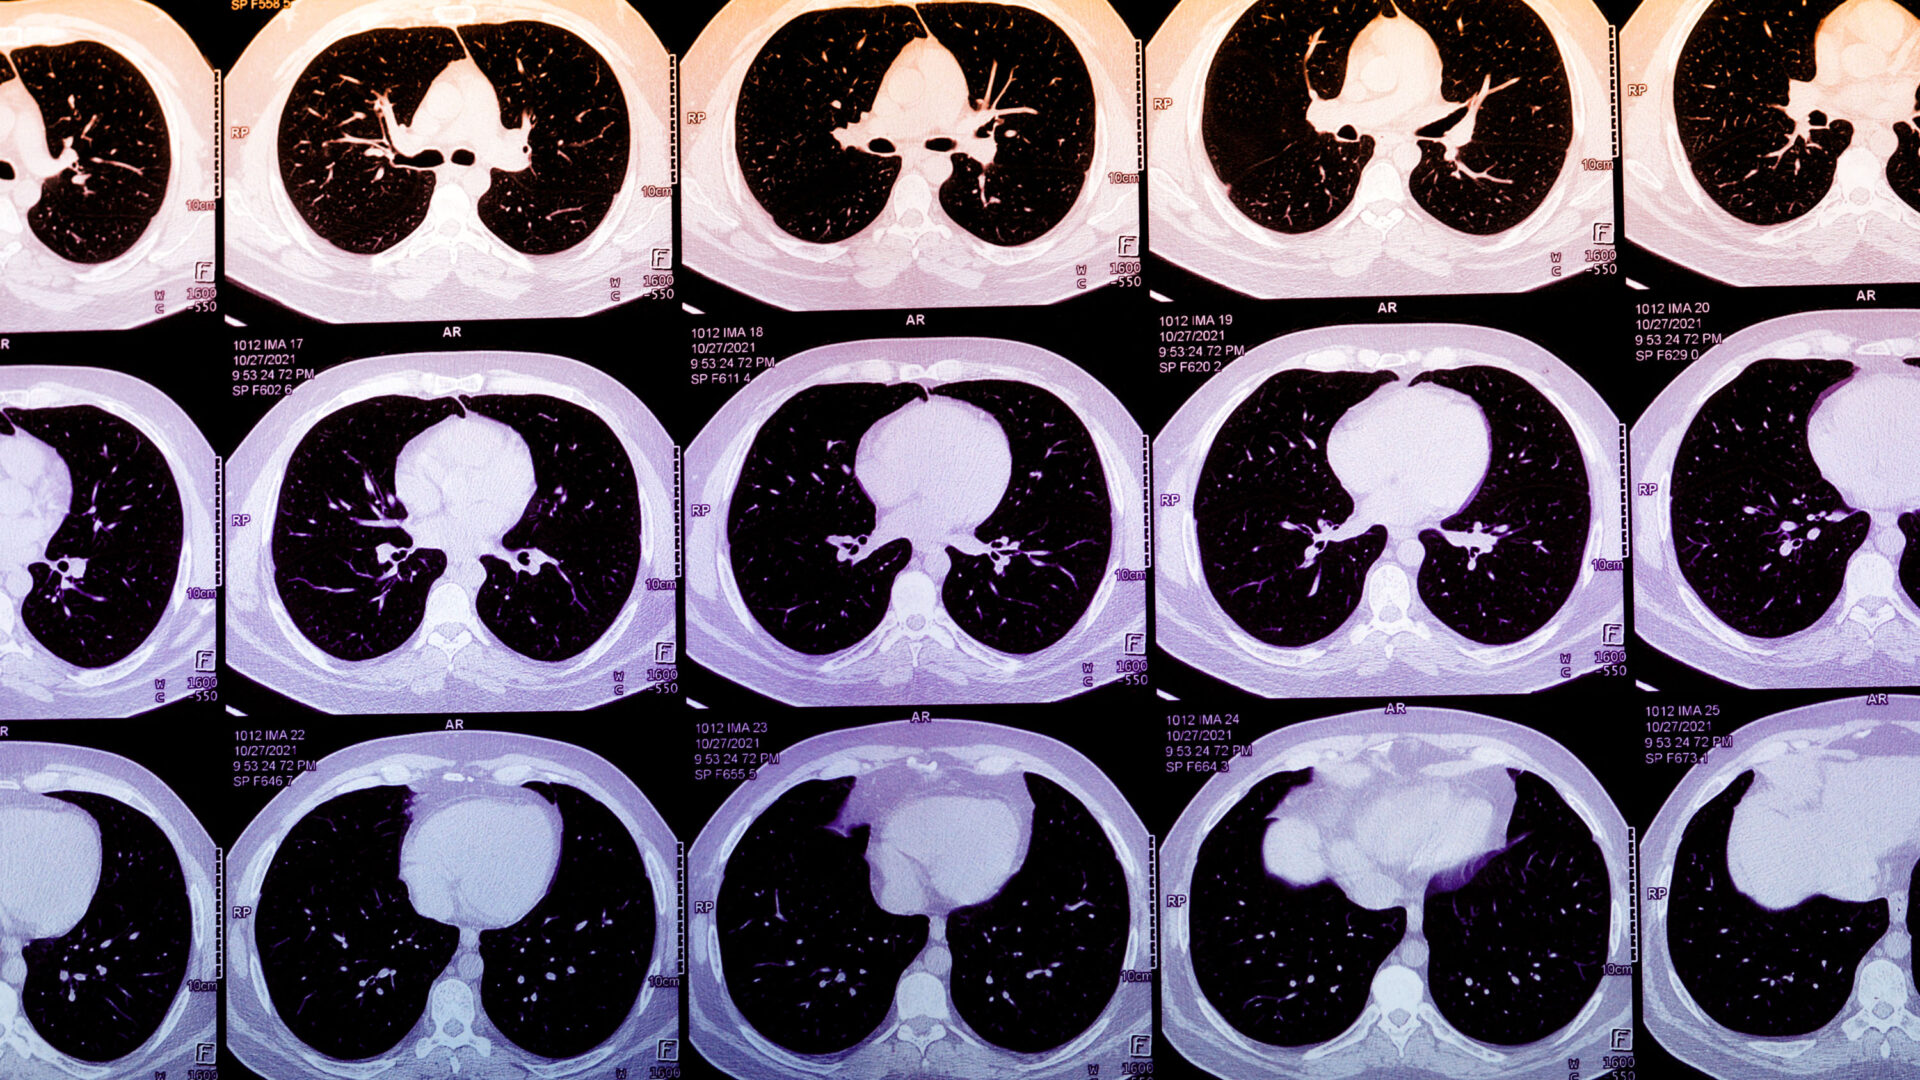

Las pruebas específicas para CAC siguen siendo un método infrautilizado para predecir el riesgo de ataque cardíaco. Durante décadas, la placa en las arterias del corazón avanza a través de su propio ciclo de vida, endureciéndose desde residuos ricos en lípidos hasta calcio. Los ataques cardíacos en sí generalmente ocurren cuando una placa más joven y rica en lípidos se rompe de manera impredecible, lo que desencadena una cascada de inflamación que finalmente bloquea el suministro de sangre al corazón. La placa calcificada es generalmente estable, pero encontrar CAC sugiere que es probable que también esté presente una placa más joven y más propensa a romperse.

También está la cuestión de si estas puntuaciones generadas por IA realmente mejorarían la atención al paciente. Para un paciente sintomático, una puntuación CAC de cero puede ofrecer una falsa tranquilidad. Para el paciente asintomático con una puntuación CAC alta, los próximos pasos siguen siendo inciertos. Más allá de las estatinas, no está claro si estos pacientes se beneficiarían al comenzar con costosos medicamentos para reducir el colesterol como Repatha u otros inhibidores de PCSK9. Puede alentar a algunos a seguir procedimientos posteriores innecesarios pero costosos que incluso podrían terminar causando daño. Actualmente, ni Medicare ni la mayoría de las aseguradoras reembolsan la puntuación CAC derivada de la IA como un servicio separado. El argumento comercial actual para esta tecnología radica, efectivamente, en estos incentivos potencialmente perversos.